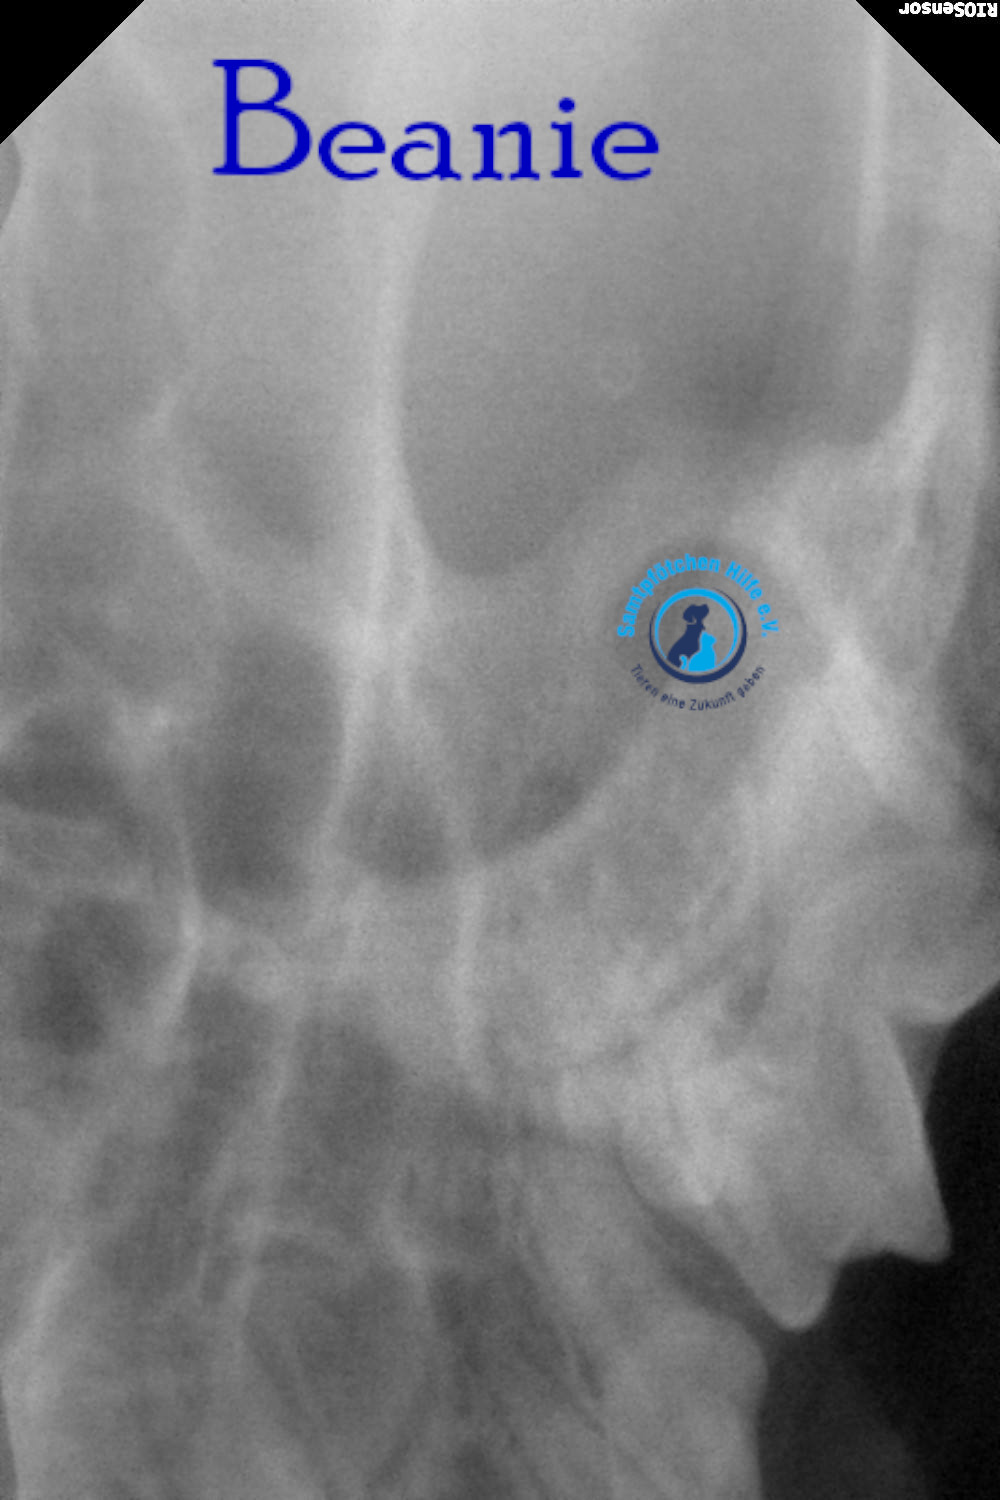

Unsere Beanie hat immer noch Probleme mit der Nasenatmung und musste deshalb zum Tierarzt. Der Arzt nahm Blut für allgemeine Indikatoren und Biochemie sowie PCR für Leukämie und Immunschwäche ab. Auch die Ohren wurden sorgfältig untersucht; Manchmal behindern Polypen in den Ohren die Atmung, aber die Ohren waren sauber. Der Arzt untersuchte auch den Rachenraum. Aufgrund der Untersuchungsergebnisse wurde eine Computertomographie des Gehirns im Bereich der Nase und des Nasenrachens sowie eine tägliche Zahnreinigung verordnet – bei Beanie besteht der Verdacht auf eine juvenile Stomatitis. Wenn Sie jetzt nicht mit der Zahnbehandlung beginnen, müssen in 2-3 Jahren alle Zähne gezogen werden.

Lyudmila schreibt: "Die Ärzte vermuteten, dass etwas in Beanies Nasenrachenraum feststeckte, ein Fremdkörper, der sie am Atmen hinderte. Sie führten eine Operation durch, führten eine Sonde tief ein und spülten sie aus, konnten aber nichts finden. Eine Röntgenaufnahme zeigte leichte Veränderungen in einer Nasennebenhöhle. Außerdem wurde Material aus der Nasenschleimhaut für eine Zytologie entnommen. Das Fazit des Zytologen: Das Material könnte auf einen Polypen in der Nase hinweisen. Da Binis Nasengänge sehr eng sind, ist eine Rhinoskopie möglicherweise nicht möglich. Bisher wurden Hormontropfen in die Nase empfohlen, die aber kaum helfen. Eine Konsultation mit einem Chirurgen, der Rhinoskopie durchführt, ist erforderlich; unsere Tierklinik führt diese Untersuchung nicht durch.